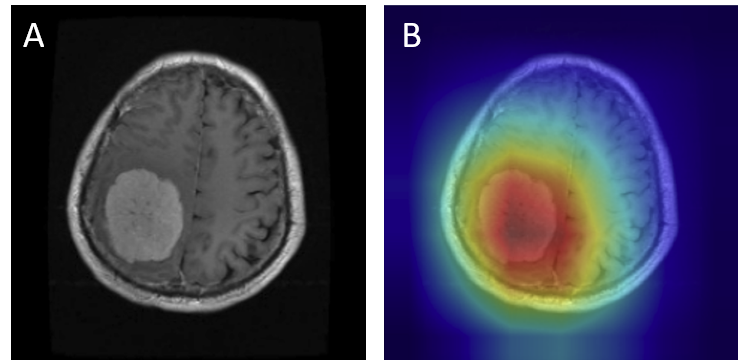

Grad-CAM visualizations of correctly classified cases confirm that the model focuses on regions consistent with radiological expectations. In these overlays, warmer colors (red and orange) highlight the areas where the network places the greatest emphasis during prediction, while cooler colors (blue) correspond to regions with minimal contribution. This distinction allows direct inspection of whether the model bases its decision on clinically relevant cues.

For gliomas, the heatmaps align with intra-axial lesions exhibiting infiltrative margins (Figure 8). Meningiomas are accurately identified at dural or peripheral attachment sites, consistent with their extra-axial presentation (Figure 9). Pituitary adenomas are localized to the sella turcica with concentrated red activation at the lesion boundaries (Figure 10). Finally, in no tumor cases, the activation maps remain diffuse or midline-focused without strong hotspots, consistent with normal anatomy (Figure 11). The correspondence between the model's attention and radiological landmarks indicates that the network is learning meaningful diagnostic features rather than relying on spurious correlations.

Figure 11: No tumor — original (A) vs. Grad-CAM (B), correct model prediction.

No Tumor Correct